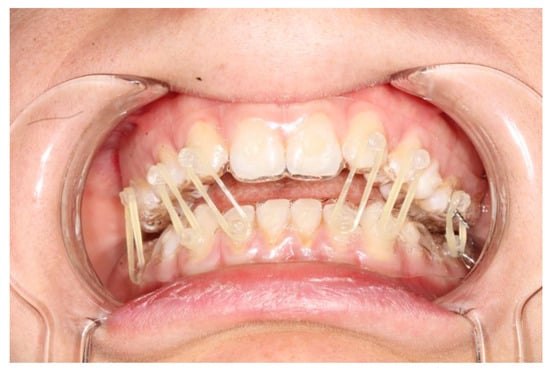

The splints were bonded to the teeth with a restorative flowable composite (Filtek Supreme Flowable, 3M, St. Paul, MN, USA), which was applied through the holes designed on the splint (Figure 1 and Figure 2).

The fixation strength of the intermaxillary fixation was considered adequate in both cases (Figure 5 and Figure 6).

Figure 1. Intraoral view of patient 2. It is possible to see the coronal fracture of element 4.2; the fitting of the splints is adequate and so is the fixation.